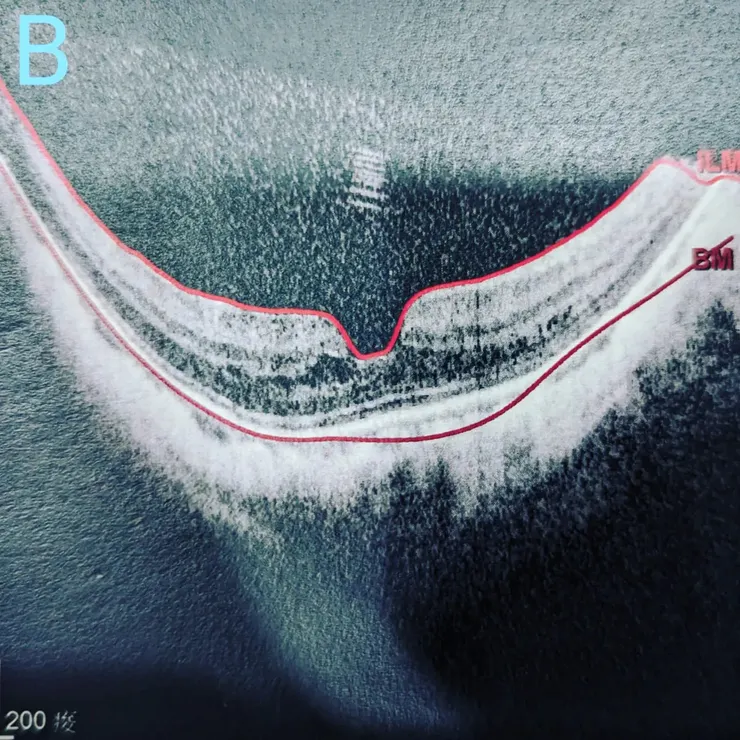

這次的手術病人是Dr.G的大學同學的媽媽,同學媽媽本身是高度近視病人,原本近視度數雙眼就在1600度左右,而右眼更因為白內障影響,術前檢查量到2200度的近視度數(圖A),眼軸長均超過30mm(正常人平均應該為22-24mm),且因為眼軸過長已經在黃斑部產生視網膜分裂(圖B)。